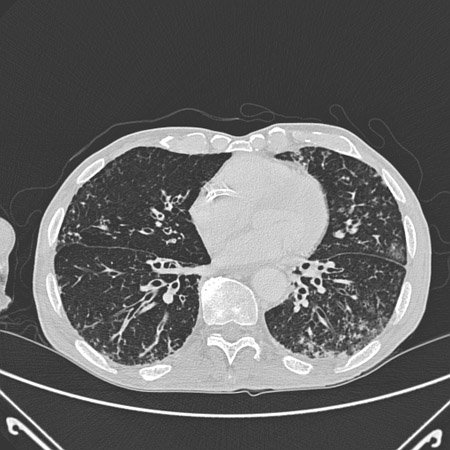

Exploración por TC de tórax de un paciente con toxicidad pulmonar por amiodarona, que muestra opacidades asimétricas con una distribución periférica

De la colección personal del Dr. A. Pataka y el Profesor P. Argyropoulou, Aristotle University, Thessaloniki, Grecia